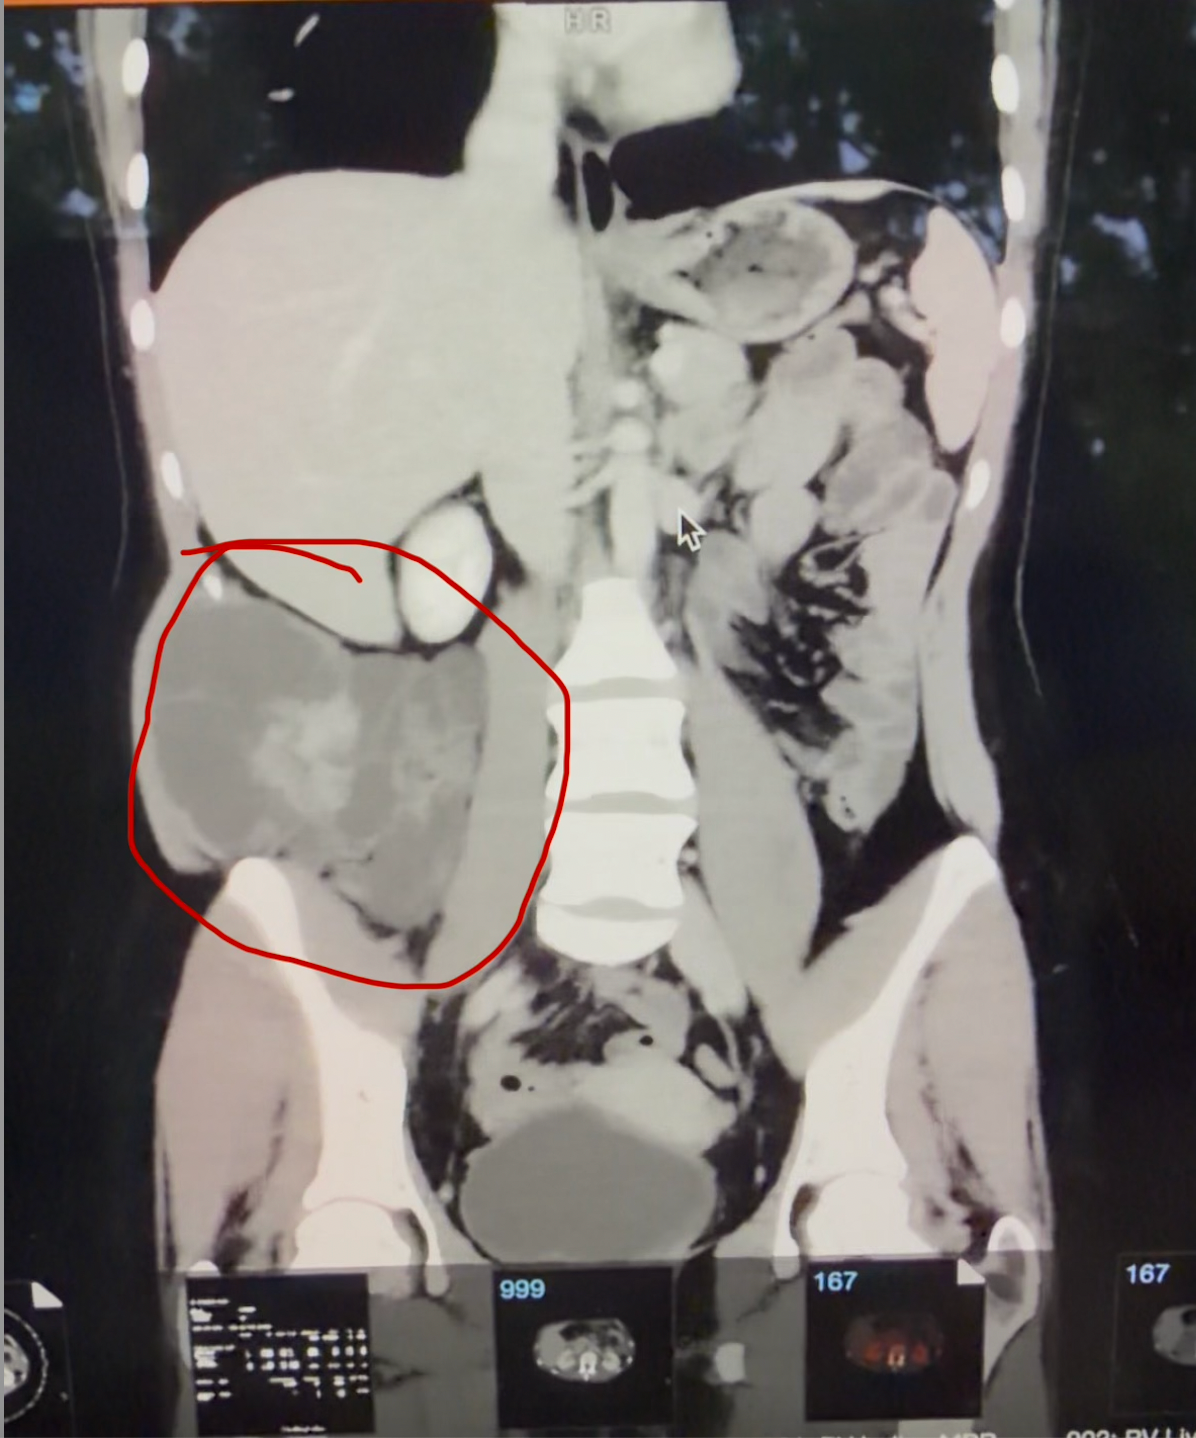

As some people may know, Zora got some unfortunate news over the last few days, receiving a Sarcoma cancer diagnosis early this week. As this is Zora's last semester at Mount Holyoke, this came as a huge shock and also brought on many new and unexpected expenses. Through your help, your donations will help with accommodations near Massachusetts General Hospital, food, and travel for Zora's family to get from Kansas to Boston. As this is just the beginning of a possible treatment plan with chemotherapy, radiation, and surgery, anything and everything will help at this time!